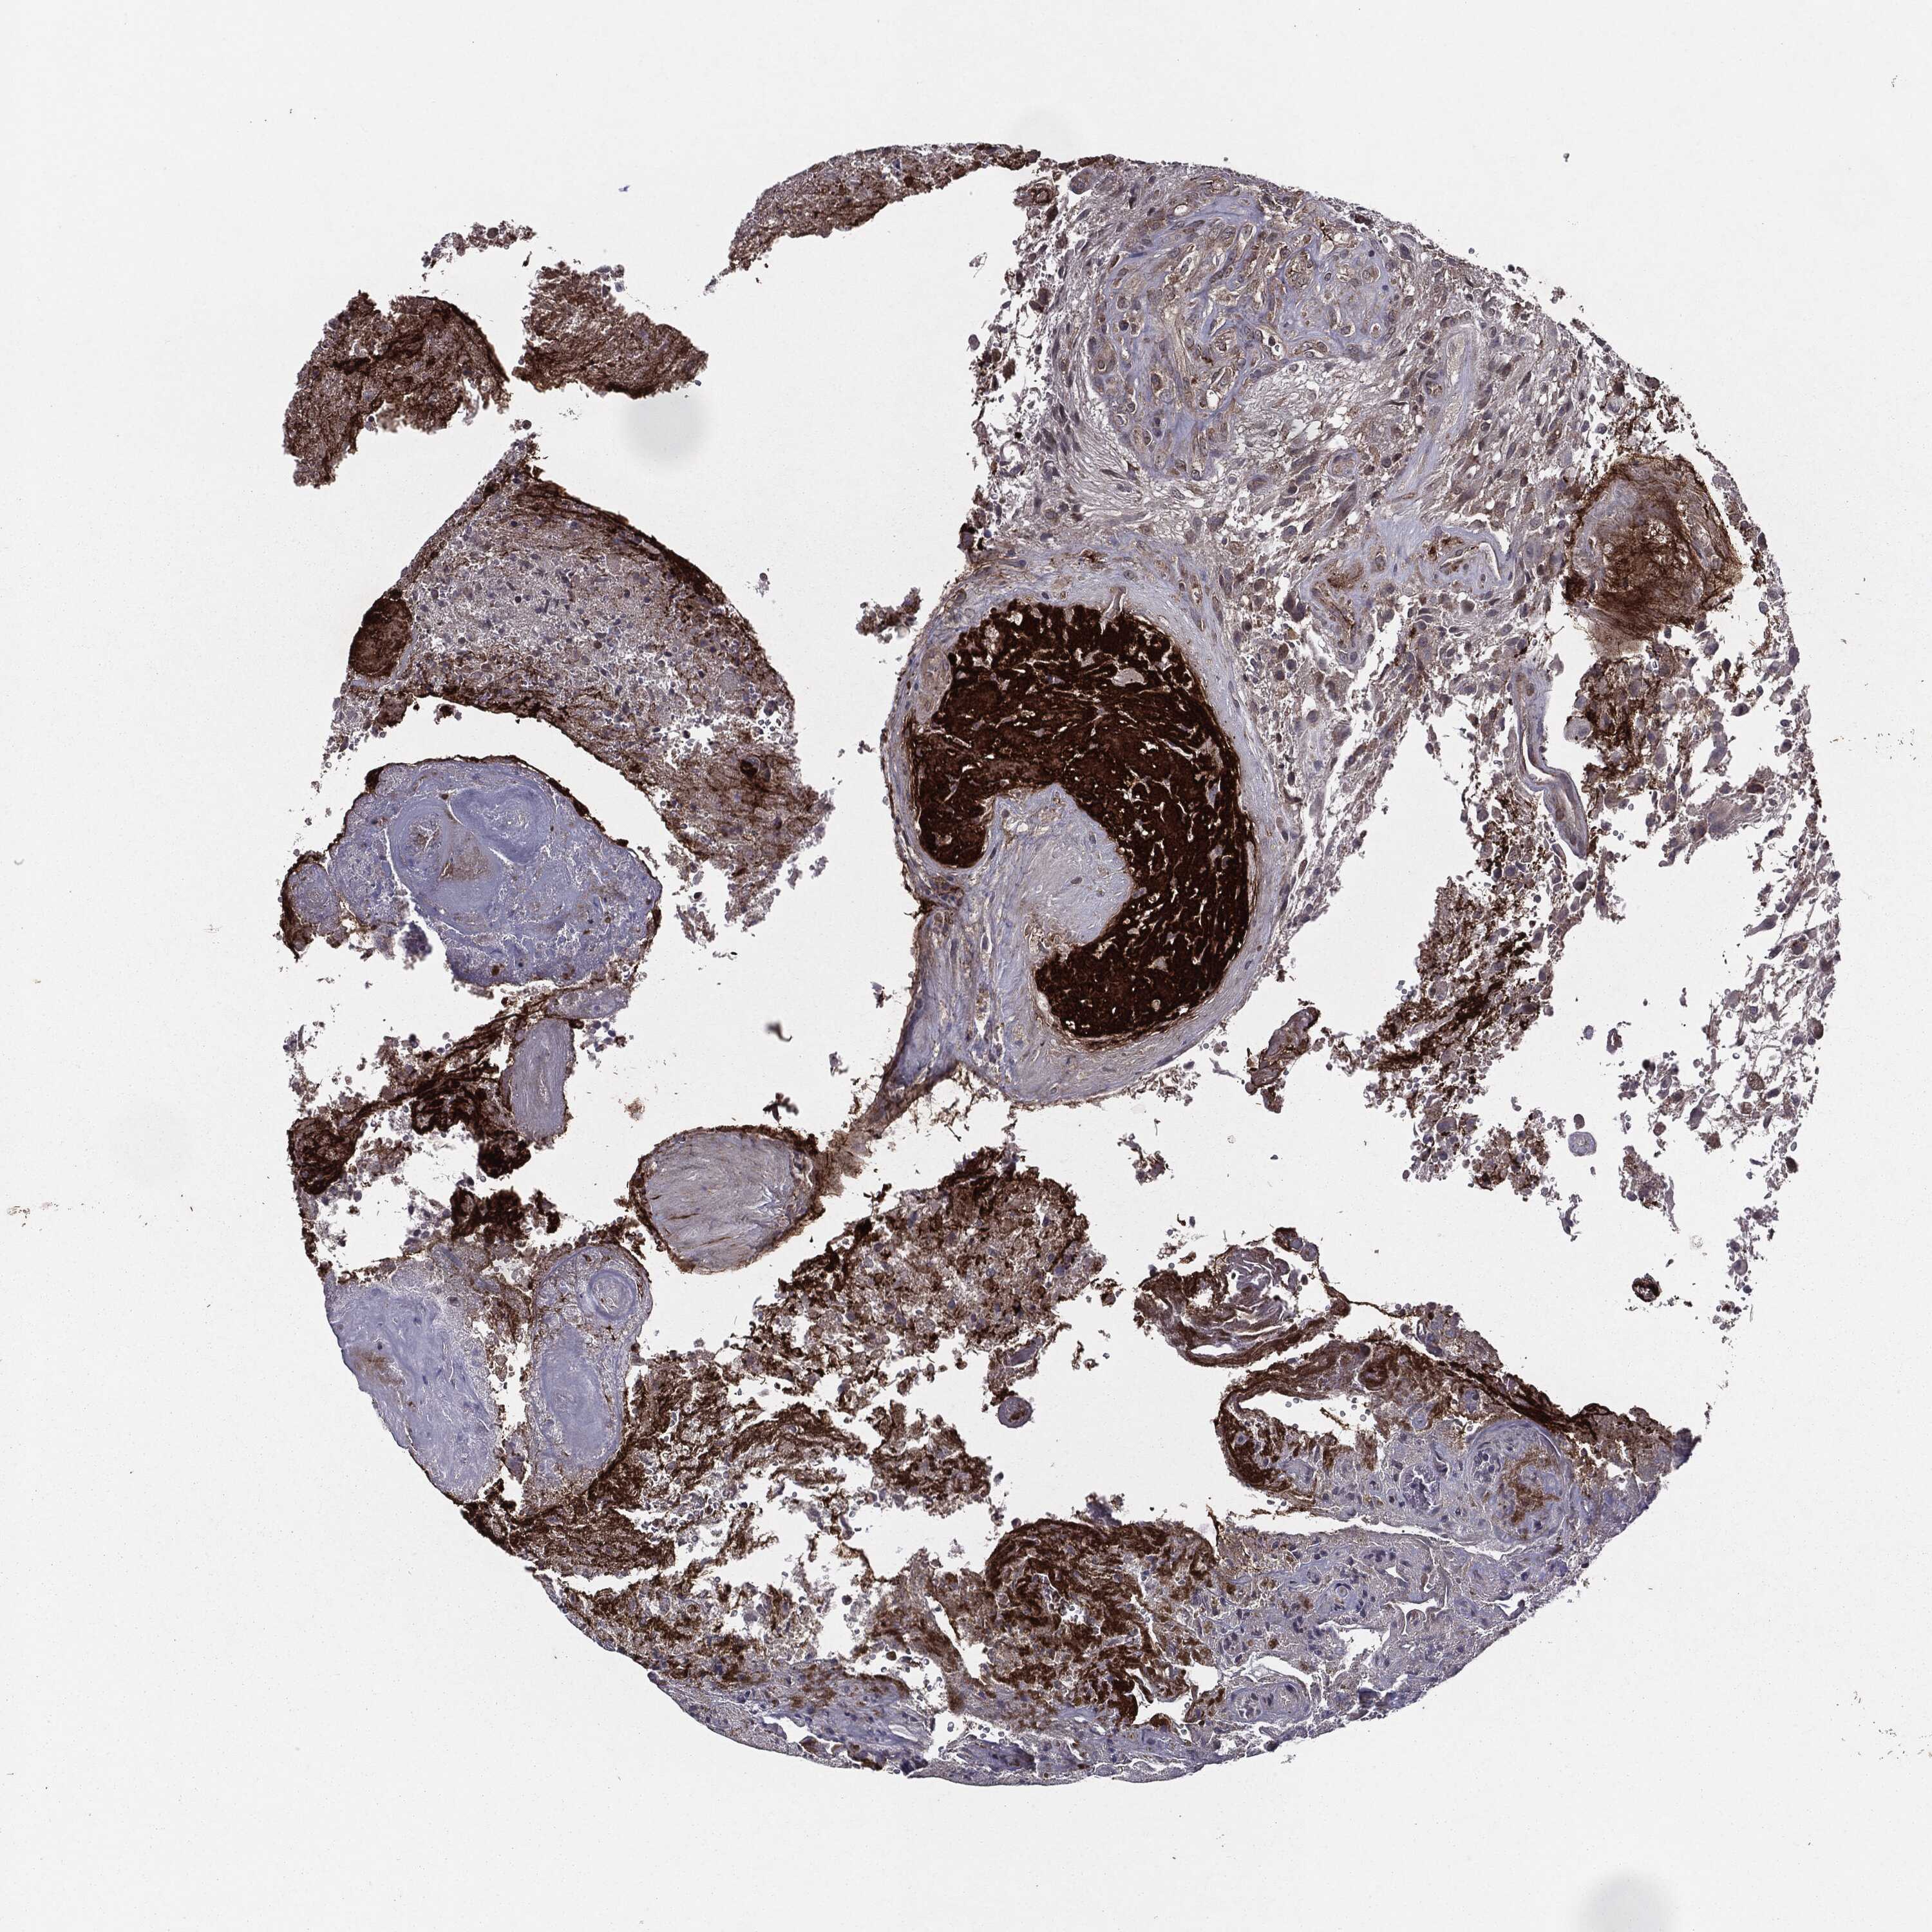

GLIOMA - Protein expressioni

A mouse-over function shows sample information and annotation data. Click on an image to view it in a full screen mode. Samples can be filtered based on level of antibody staining by selecting one or several of the following categories: high, medium, low and not detected. The assay and annotation is described here.

Note that samples used for immunohistochemistry by the Human Protein Atlas do not correspond to samples in the TCGA dataset.

Antibody stainingi

Antibody staining in the annotated cell types in the current human tissue is reported as not detected, low, medium, or high, based on conventional immunohistochemistry profiling in selected tissues. This score is based on the combination of the staining intensity and fraction of stained cells.

Each image is clickable and will lead to virtual microscopy that enables deeper exploration of all samples and also displays staining intensity scores, fraction scores and subcellular localization as well as patient and tissue information for each sample.

Antibody HPA052606

Antibody HPA077139

Glioma, malignant, Low grade

Glioma, malignant, High grade

Glioma, malignant, NOS